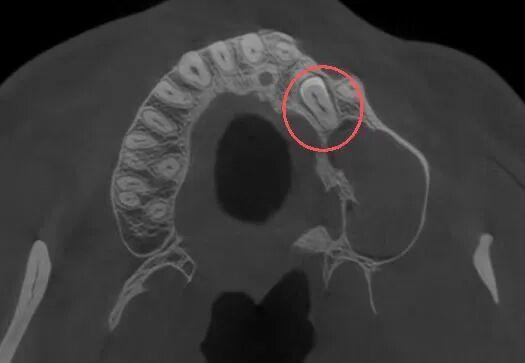

口腔颌面外科医生为其进行了详细的口腔检查并拍了放射片,结果显示:张先生的牙齿属于腭向埋伏阻生双尖牙,更值得注意的是,他的左侧上颌窦底还长有一个丘状软组织囊肿,且阻生牙的牙根与囊肿底部关系十分密切。

“阻生牙是牙齿萌出过程中因空间不足、遗传、感染等多种因素导致的异位埋伏,而上颌窦囊肿则是上颌窦内常见的良性病变,两者同时出现且位置紧密关联,若不及时处理,可能会引发囊肿增大、骨质破坏、上颌窦炎等问题。”口腔颌面外科病房主任孙超解释道。